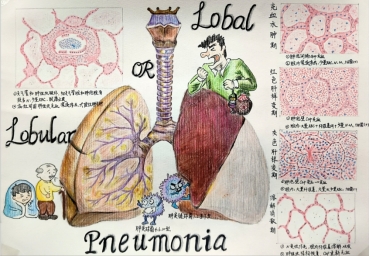

作品名:《Lobar or LobularPneumonia(大/小叶性肺炎)》

作者:时新茹

指导老师:王宁

作品简介:本作品描绘了细菌性肺炎中大叶性肺炎和小叶性肺炎的各方面比较。本作品所表现出的有以下:第一、发病的部位不同,大叶性肺炎呈段或者肺大叶分布,而小叶性肺炎发生在肺小叶或在支气管周围;第二、发病的原因,大叶性肺炎多是肺炎链球菌1.2.3.7型,而小叶性肺炎大多混杂菌肺炎,主要是肺炎链球菌4.6.10型;第三、发病的性质,大叶性肺炎主要是肺泡腔内纤维素性炎,有特色的四期病程划分,而小叶性肺炎是化脓性肺炎;第四、发病的年龄,大叶性肺炎常见于青壮年,而小叶性肺炎多发生在幼儿或者老年人。